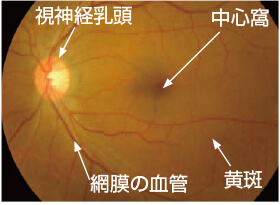

眼の構造と働きについて

私たちが物を見る、つまり外から眼に光が入ったとき、その情報は角膜→瞳孔→水晶体→硝子体と通過していき、最後に網膜に像が結ばれます。そこから視神経を介して情報が脳に伝わり、私たちは「見た」と感じます。 眼は、よくフィルムカメラに例えられます。水晶体がレンズにあたり、網膜はフィルムにあたるという関係ですね。

私たちが物を見る、つまり外から眼に光が入ったとき、その情報は角膜→瞳孔→水晶体→硝子体と通過していき、最後に網膜に像が結ばれます。そこから視神経を介して情報が脳に伝わり、私たちは「見た」と感じます。 眼は、よくフィルムカメラに例えられます。水晶体がレンズにあたり、網膜はフィルムにあたるという関係ですね。

黄斑・中心窩について

黄斑とは、網膜の中心部にあり、視力ともっとも深いかかわりを持っています。物を見たときのその物の大きさや形、奥行きなど、視覚情報の大半が、黄斑で認識されています。ここで障害が起こると、当然ながら視力の低下が引き起こされます。 黄斑のさらに中心には、「中心窩」があります。こちらはさらに重要な部分であり、障害されたときにはより大幅な視力低下を招きます。

黄斑とは、網膜の中心部にあり、視力ともっとも深いかかわりを持っています。物を見たときのその物の大きさや形、奥行きなど、視覚情報の大半が、黄斑で認識されています。ここで障害が起こると、当然ながら視力の低下が引き起こされます。 黄斑のさらに中心には、「中心窩」があります。こちらはさらに重要な部分であり、障害されたときにはより大幅な視力低下を招きます。

眼底の正面図(正常な眼)

黄斑の範囲については、厚生労働省の網膜脈絡膜・視神経萎縮症研究班による『加齢黄斑変性の分類と診断基準』に準拠しています。

黄斑の範囲については、厚生労働省の網膜脈絡膜・視神経萎縮症研究班による『加齢黄斑変性の分類と診断基準』に準拠しています。

写真提供:日本大学 湯澤 美都子先生

正常な眼の眼底写真